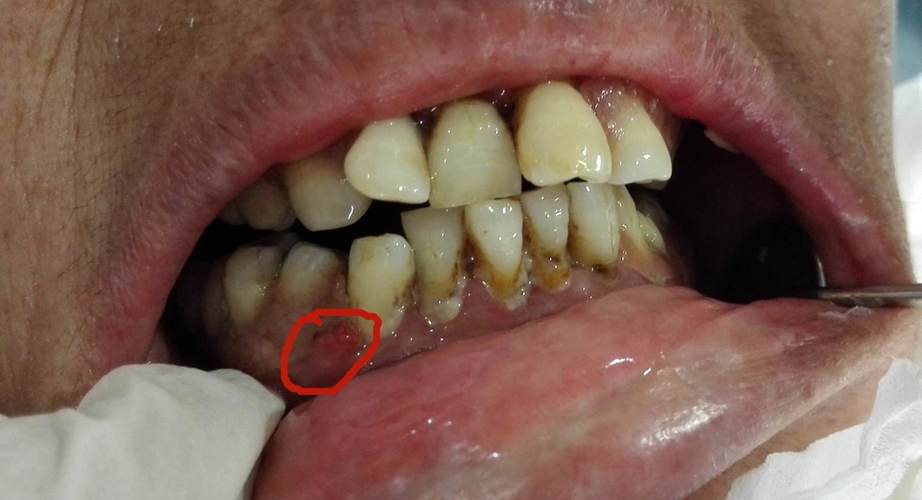

健康牙龈呈粉红色,质地坚韧且贴合牙面,而牙龈炎患者的牙龈常出现明显异常,首先是颜色变化,牙龈会从正常的粉红色变为鲜红色或暗红色,严重时可能呈现紫红色,这是由于牙龈组织内血管扩张、充血导致的,其次是形态改变,牙龈边缘会变厚、肿胀,失去原有的坚韧质地,变得松软而脆弱,轻轻触碰时容易出血,牙龈表面可能变得光滑发亮,或因组织水肿而呈现“圆钝”状,失去与牙齿之间的锐利边缘,原本紧贴牙面的牙龈也会与牙齿分离,形成“假性牙周袋”,容易积存食物残渣和细菌,进一步加重炎症。

牙龈出血是牙龈炎最典型且最早出现的症状,也是患者最常察觉的异常,初期多表现为刷牙或使用牙线时牙龈少量出血,表现为牙刷毛或牙线上有鲜红色血迹,有时漱口时也会带出血丝,随着病情进展,即使不进行机械刺激(如咀嚼硬物、吮吸),牙龈也可能自发性出血,严重时甚至会出现口腔异味(口臭)、牙龈疼痛等症状,出血的机制主要是牙菌斑中的细菌及其代谢产物(如内毒素)刺激牙龈组织,导致毛细血管通透性增加、脆性增大,轻微外力即可引起血管破裂出血。